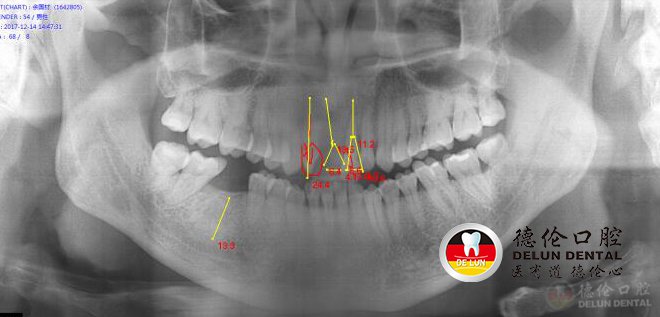

患者简介: 余先生 54岁

牙齿情况:上颌缺牙2颗,下颌缺牙1颗

余先生术前口腔X光片